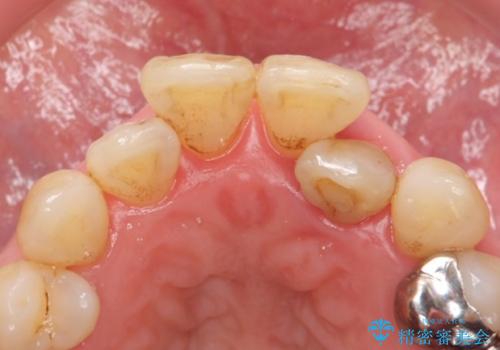

精査したところ、前歯の咬み合わせが反対になっていること、下の奥歯(下顎両側67)が4本欠損していることから動揺が生じていました。

入れ歯も抵抗があるとのことから、相談を重ね、今の状態では保存不可能な下の前歯(左下2)を抜去し、ブリッジや連結補綴により動揺を抑えることにしました。

また、咬み合わせが反対になっている上の前歯(左上2)も補綴で形を変えることにより、咬合を改善しました。